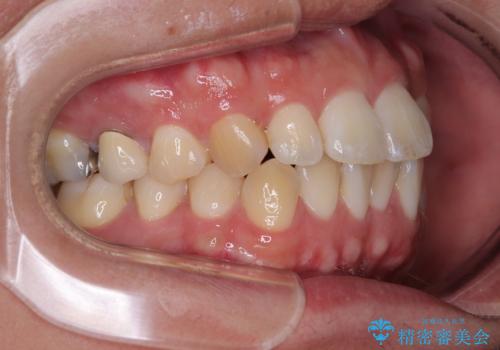

前歯のデコボコをささっと治す 短期間でのインビザライン矯正治療

- 前歯の反対咬合などを気にして来院された患者様です。

ワイヤー矯正、マウスピース矯正どちらでも対応可能であったので、ご本人の希望によりインビザラインにて矯正治療を行うこととしました。

毎日の装着時間をしっかりと守ってくださり、1年強の短期間で、あっという間に治療を終えることができました。